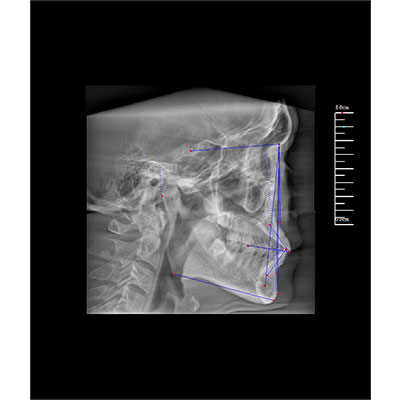

高清口腔三維CT/全景影像 PLX3000A

該款牙科CBCT產(chǎn)品采用動態(tài)平板探測器,獲得三維圖像的同時還具有數(shù)字化全景功能,廣泛應用于口腔頜面外科、正畸科、正頜外科、種植科、牙體科、顳下頜關(guān)節(jié)科等術(shù)前術(shù)后。

專有三維重建算法,可提供任意位置高清斷層影像。

可同時觀察軸向面、冠狀面和矢狀面圖像,方便臨床診斷。